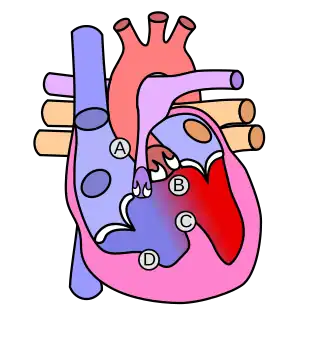

Helen B. Taussig is known as the founder of pediatric cardiology. She became famous through her work with Tetralogy congenital heart defect in which oxygenated and deoxygenated blood enters the circulatory system resulting from a ventricular septal defect (VSD) right beneath the aorta. This condition causes newborns to have a bluish-tint, cyanosis, and have a deficiency of oxygen to their tissues, hypoxemia. She worked with Alfred Blalock and Vivien Thomas at the Johns Hopkins Hospital where they experimented with dogs to look at how they would attempt to surgically cure these "blue babies". They eventually figured out how to do just that by the anastomosis of the systemic artery to the pulmonary artery and called this the Blalock-Taussig Shunt.[18]

Tetralogy of Fallot, pulmonary atresia, double outlet right ventricle, transposition of the great arteries, persistent truncus arteriosus, and Ebstein's anomaly are various congenital cyanotic heart diseases, in which the blood of the newborn is not oxygenated efficiently, due to the heart defect.

Tetralogy of Fallot

Tetralogy of Fallot is the most common congenital heart disease arising in 1–3 cases per 1,000 births. The cause of this defect is a ventricular septal defect (VSD) and an overriding aorta. These two defects combined causes deoxygenated blood to bypass the lungs and going right back into the circulatory system. The modified Blalock-Taussig shunt is usually used to fix the circulation. This procedure is done by placing a graft between the subclavian artery and the ipsilateral pulmonary artery to restore the correct blood flow.